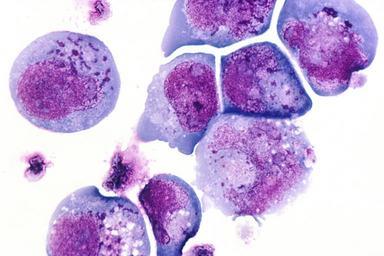

MAKE A MEME View Large Image HHV-6 inclusion bodies.jpg This is a histological slide of the human herpes virus-6 HHV-6 previously known as HBLV a type of herpes virus that was discovered in October 1986 This is a photomicrograph of infected cells with inclusion bodies ...

Keywords: HHV-6 inclusion bodies.jpg This is a histological slide of the human herpes virus-6 HHV-6 previously known as HBLV a type of herpes virus that was discovered in October 1986 This is a photomicrograph of infected cells with inclusion bodies in both the nucleus and the cytoplasm The slide is stained with H E Subjects names Topics/Categories Pathology -- Histology Type Color Print Color Slide Source Author AV Number AV-8610-3057 Date Entered 1/1/2001 Access Public Zaki Salahuddin Laboratory of Tumor Cell Biologyhttp //visualsonline cancer gov/details cfm imageid 2252 Date Created October 1986 Unknown photographer/artist PD-USGov Human histopathology Human herpesvirus 6